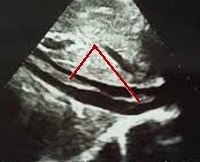

• Трансвагинальное УЗИ малого таза. При ТВУЗИ тромбы в яичниковой вене визуализируются в виде аваскулярных низко- или среднеэхогенных включений, частично или полностью перекрывающих просвет сосуда. Могут определяться кальцинаты (флеболиты).